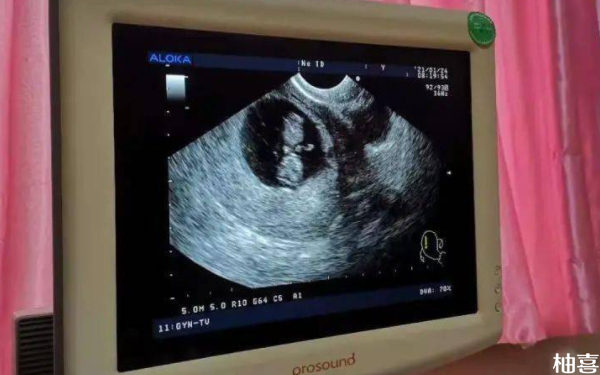

孕后期b超单子看男女图解怎么看?

孕后期的b超单子不能看男女,所以不存在“怎么看”的说法。从科学角度来讲,B超为二维灰阶超声,属于超声检查技术的一种。在孕期做B超检查,孕妇可以知道胎儿的发育情况。另外,需注意,我国法律禁止非医学必要的胎儿性别鉴定,因此,建议孕妇和家属不要过分关注男女性别,而是应该关注其健康和发育情况,并积极帮助胎儿生长。